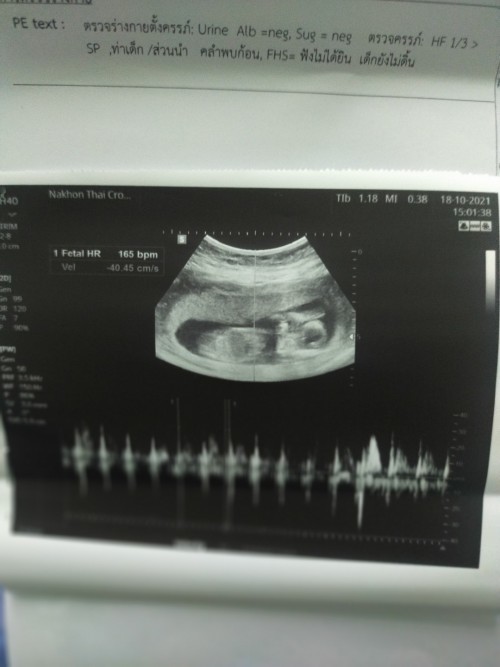

ตอนนี้10wแล้วจ้า

เห็นชัดแล้วค่ะ